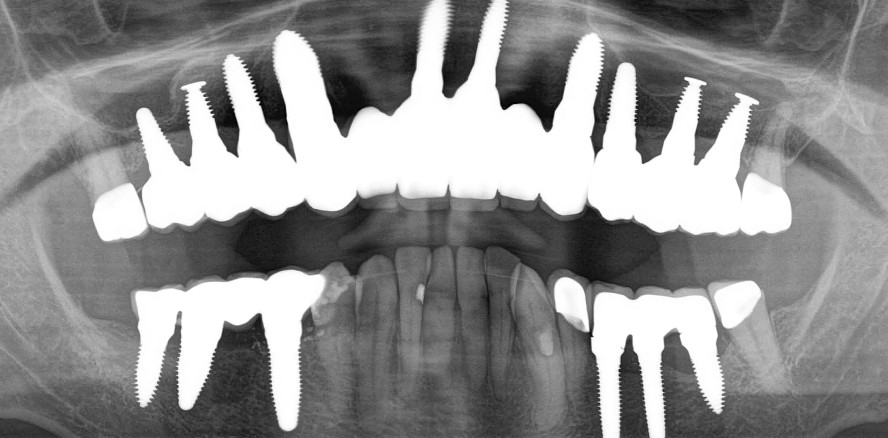

Implantologie 12.05.2020

Biologische GBR und Keramikimplantate – Teil 1

Heutzutage gibt es immer noch viele Patienten, die in der Folge von Zahnextraktionen signifikant Knochenvolumen verloren haben und bei denen deshalb Knochenaufbaumaßnahmen erforderlich sind. Im folgenden Artikel werden einige dieser Maßnahmen dargestellt – mit Schwerpunkt auf der Verwendung von autologen Materialien.

Keramikimplantate, respektive Zirkoniumdioxid-Implantate, bestehen aus der Hochleistungskeramik Zirkoniumdioxid. Dies bedeutet, dass das Material in oxidierter Form vorliegt und somit „ausreagiert“ ist,1 also keine freien (Bindungs-)Elektronen aufweist und somit überaus reaktionsträge ist.2 Es sind Temperaturen von über 2.600 °C oder die Anwendung von Flusssäure erforderlich, um das Material zu verändern. Im Vergleich zu Titan ist die geringere Plaqueaffinität, die fehlende thermische und elektrische Leitung sowie die Korrosionsstabilität des Zirkons von großem Vorteil.2–9 Bei der Einheilung von Zirkoniumdioxid-Implantaten werden vermutlich geringe inflammatorische Botenstoffe ausgeschüttet.1,10–13 In Studien konnte gezeigt werden, dass der Bone-to-Implant-Contact (BIC) von Zirkoniumdioxid dem von Titan ebenbürtig ist.14–20

Bei Titan entsteht bei Insertion der Implantate mit hoher Friktion ein Abrieb und im weiteren Verlauf durch den Vorgang der (Bio-)Korrosion eine Abgabe von Titandioxidpartikeln in das umliegende Hart- und Weichgewebe, wodurch Makrophagen aktiviert werden.21–29 Diese Aktivierung kann zu einer Ausschüttung von Zytokinen wie TNF-α und IL-1-β führen, was lokale Reaktionen und chronische Entzündungen („Silent Inflammation“) hervorrufen kann. Insbesondere die Aktivierung von Osteoklasten löst einen Knochenabbau im Sinne einer Periimplantitis aus.30 Es gilt, zu beachten, dass Keramikimplantate schlechte thermische Leiter sind und nicht mit zu hohen Eindrehmomenten inseriert werden sollten, da die an der Oberfläche entstehende Reibungshitze nicht an den Kern abgeleitet wird. Deshalb ist das vom Erstautor entwickelte Keramikimplantat (SDS Swiss Dental Solutions) so gestaltet, dass die gesamte Friktion und Stabilität aus dem apikalen Anteil und seinem tiefen und schneidenden Gewinde gewonnen und bei korrekter Anwendung des Bohrprotokolls das Risiko einer Überhitzung der Kompakta reduziert wird.

Im krestalen Anteil des Knochens wird mit dem letzten Bohrer, dem Countersink, überextendiert aufbereitet und somit Insertionsdruck auf diesen sensiblen und mindervaskularisierten Bereich vermieden.31 Der schneidende apikale Gewindeanteil ermöglicht es auch, dass das Implantat im Falle einer bindegewebigen Einheilung in über 80 Prozent der Fälle auf > 35 Ncm „nachgedreht“ werden kann. Dieses Verständnis für die physikalischen, biologischen und immunologischen Eigenschaften des Zirkoniumdioxids ist sehr wichtig, wenn wir über Knochenaufbaumaßnahmen sprechen werden. Grundsätzlich ist die Durchführung solcher Maßnahmen in den Kliniken der Autoren immer seltener geworden, da aufgrund der vorgenannten Eigenschaften in vielen Fällen Sofortimplantate inseriert werden können. Zirkon neigt vermutlich selbst in zuvor hochgradig entzündeten Arealen unter Beachtung eines eingehaltenen Begleitprotokolles (THE SWISS BIOHEALTH CONCEPT) nicht dazu, weitere Entzündungen auszulösen. Dennoch gibt es immer noch viele Patienten, welche in der Folge von Zahnextraktionen in der Vergangenheit signifikant Knochenvolumen verloren haben und bei denen deshalb Knochenaufbaumaßnahmen erforderlich sind. Die Autoren werden im Folgenden die entsprechenden, in der SWISS BIOHEALTH CLINIC angewendeten Maßnahmen mit Schwerpunkt auf der Verwendung von autologen Materialien darstellen.